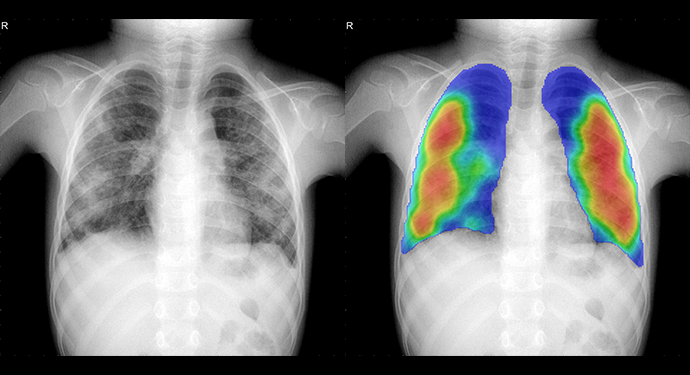

The input and output are still the same: CAD4TB processes frontal chest radiographs from any type of digital X-ray equipment and produces a heatmap, indicating with colours which parts of the lungs are likely abnormal, and a score between 0 and 100. The higher the score, the more likely that the subject on the image has tuberculosis (TB).

Figure 3. Two examples of chest radiographs of children both four years old. The left image is normal, and no abnormal regions are seen in the heatmap. The score of CAD4TB version 6 for this case is 22. The right image has clear abnormalities, accurately detected by CAD4TB 6. The image gets a score of 86.